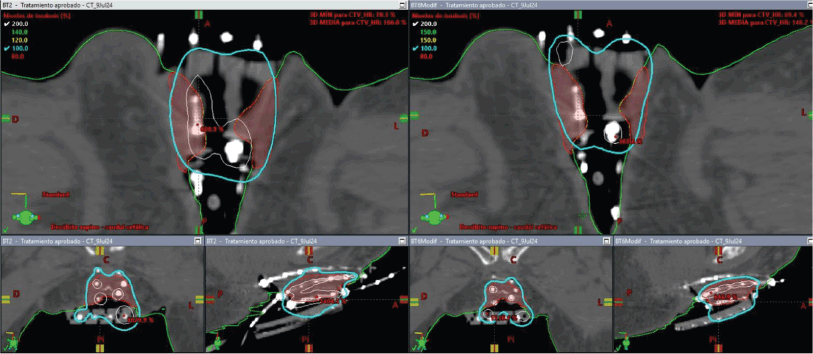

On the day of implant, the patient underwent spinal anesthesia, and a Foley catheter was placed. The custom template was positioned against the perineum, and 18 interstitial needles were inserted according to the pre-plan. An initial fraction was delivered at 8.2 Gy to the 90% isodose of the GTV (Figure 7). For subsequent fractions, the central channel was exchanged for a deeper needle to cover more cranial disease.

Figure 7. Case 2. Dose-volume histogram and dosimetric distribution of fraction #1 in axial, coronal and sagittal planes. It is shown in red CTV-HR, in orange CTV-IR, in light blue the rectum, in yellow the bladder and in purple the sigmoid colon.

Total dose was 8.2 Gy × 3 fractions, equating to roughly 48.1 Gy EQD24.5. The plan accounted for prior EBRT (30 Gy in 10 fractions). Although the bladder, rectum and sigmoid colon had some overlap with the new target volume, no dose-limiting constraints were exceeded (Table 1).